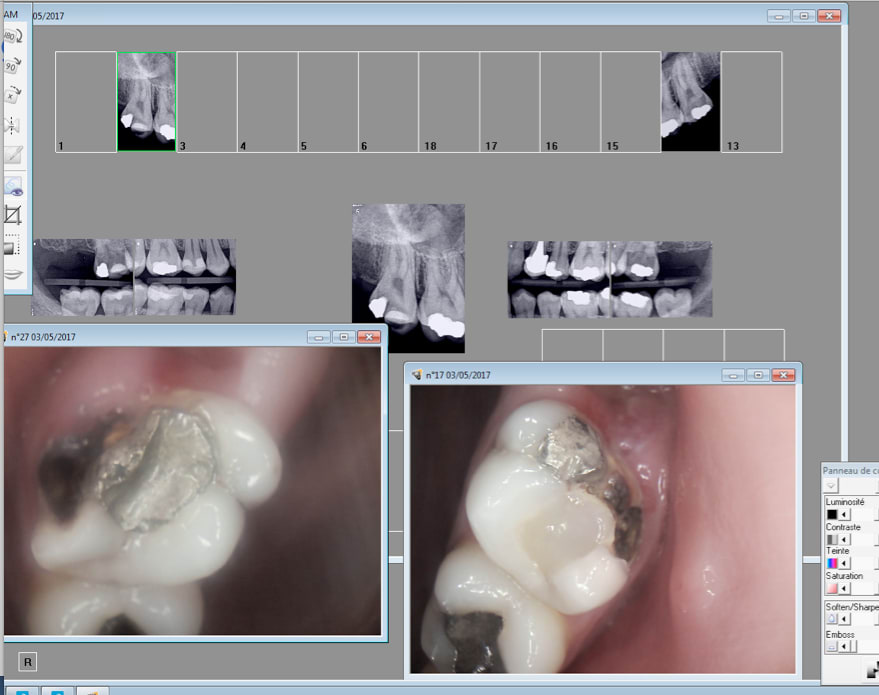

Oh merde 2 endos de plus. -)

Capture d écran 2017 05 03 09.48 - Eugenol